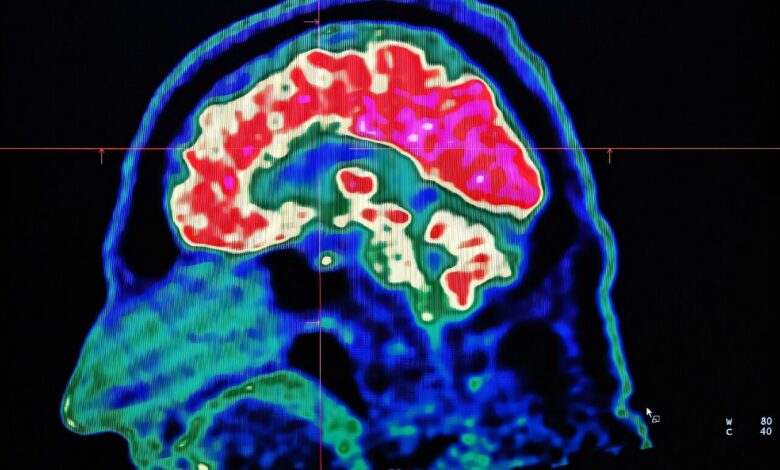

What are all these microplastics doing to our brains?

A study published in Nature Medicine raised eyebrows when it revealed the presence of microplastics in brain tissue samples from deceased individuals. Lead researcher Matthew Campen reported finding the equivalent of a plastic spoon’s worth of microplastics in the brains of the subjects. However, experts have advised caution in interpreting these findings, emphasizing the need for independent verification before drawing definitive conclusions.

The study sparked discussions about the potential effects of microplastics on human health, with some researchers questioning the validity of the results. Oliver Jones from RMIT University pointed out the lack of comprehensive data on the occurrence of microplastics globally, casting doubt on the study’s estimations. While the presence of microplastics in the brain is a concerning discovery, the study did not establish a causal link between these particles and any harmful effects.